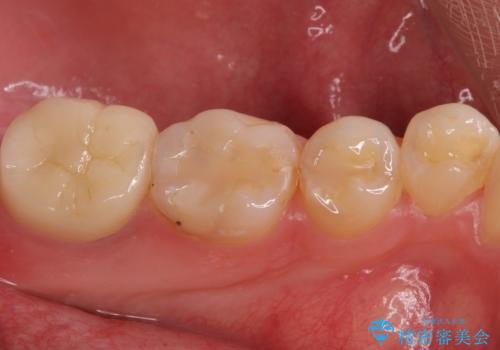

奥歯がしみる 神経を温存する治療

- 奥歯がしみるとのことで来院されました。

検査の結果、古い詰め物の裏側に虫歯ができていること(二次う蝕)が確認されたため、治療していくこととなりました。

虫歯が大きくても、今回のように神経を温存することができる場合があります。